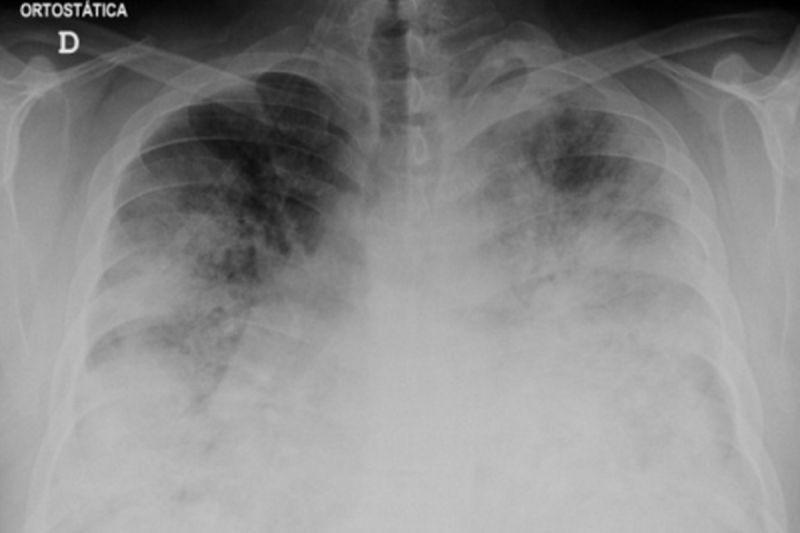

Penyakit Legionnaires adalah jenis radang paru-paru atau pneumonia yang disebabkan oleh bakteri legionella.

Menurut Organisasi Kesehatan Dunia (WHO), bentuk penularan yang paling umum adalah menghirup aerosol terkontaminasi yang dihasilkan bersamaan dengan semprotan air, emisi atau kabut dari sumber air yang tercemar.